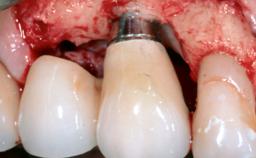

In this case, Myroslav Solonko, Ignacio Sanz Sánchez and Mariano Sanz present a treatment that aims to eliminate exposed implant threads by modifying the implant surface, converting a moderately-rough surface into a smooth surface.